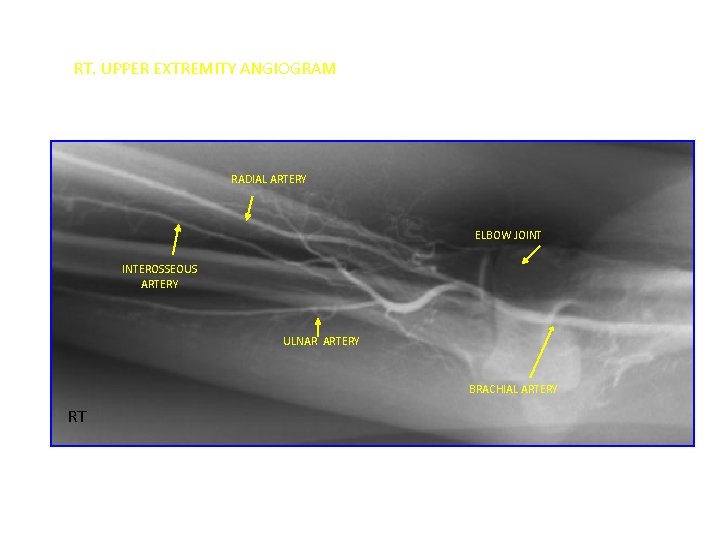

RT. UPPER EXTREMITY ANGIOGRAM RADIAL ARTERY ELBOW JOINT INTEROSSEOUS ARTERY ULNAR ARTERY BRACHIAL ARTERY RT